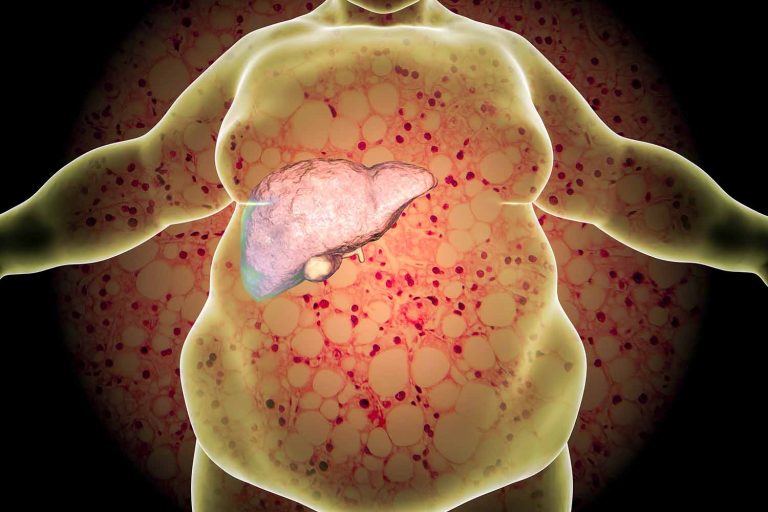

Prof. Stadlbauer-Köllner: Der Darm ist das größte Organ des Menschen mit weit über 200 m2 Oberfläche. Er steht in einem äußerst interessanten funktionellen Zusammenhang mit der Leber, da Nährstoffe, Vitalstoffe, aber auch Signalmoleküle (Zytokine) und bakterielle Bestandteile über ein großes Blutgefäß, die Pfortader, als erstes in die Leber gelangen. Unter normalen Bedingungen treten nur wenige bakterielle Bestandteile, z. B. Endotoxine und bakterielle DNA, via Darmwand in das Blut über. Sie werden dann in der Leber rasch abgebaut. Bei einer Störung der Darmbarriere kommt es zu einem stark vermehrten Einstrom bakterieller Bestandteile in die Leber, die nicht mehr damit umgehen kann. Das führt zu entzündlichen Veränderungen im Organ und damit zu einem Leberschaden.

Prof. Frauwallner: Die letzten Statistiken zu Lebererkrankungen, die ich gelesen habe, sind wirklich erschreckend. 30 % der Mitteleuropäer leiden bereits daran, die Tendenz ist stark steigend, und ein gar nicht so geringer Anteil von angeblich 8 bis 10 % der Patienten stirbt auch an diesen Erkrankungen. Noch verwunderlicher ist aber die Tatsache, dass nicht nur Menschen, die gern dem Alkohol zusprechen, von Leberkrankheiten betroffen sind, wie man dies früher angenommen hat, sondern auch jene, die noch nie Alkohol angerührt haben, allerdings einfach gern und gut essen, zu wenig Bewegung machen usw. Viele Ärzte sind darüber besorgt, dass auch andere Organe geschädigt werden, die auf den ersten Blick gar nichts mit dem Entgiftungsorgan Leber zu tun haben. Können Sie uns das erklären?

Prof. Stadlbauer-Köllner: Bei einer Störung der Darmbarriere kommt es eben nicht nur zu einer Überlastung der Leber und zu ihrer Entzündung. Wenn die bakteriellen Produkte nicht mehr abgebaut werden können und weiter in die Blutzirkulation gelangen, dann werden Immunzellen aktiviert, die auch in anderen Organen Schaden anrichten können. Das Fettgewebe steht ebenso in in einem engen Zusammenhang mit der Leber und dem Stoffwechsel. Botenstoffe aus dem Fettgewebe, vor allem aus jenem am Bauch, können in der Leber den Zuckerstoffwechsel negativ beeinflussen und eine Form der Zuckerkrankheit auslösen. Diese wiederum führt zu einer Fetteinlagerung in den Leberzellen und somit zur Fettleber, die sich bei manchen Patienten leider zu einer Fettleberhepatitis oder Leberzirrhose entwickeln kann.

Prof. Stadlbauer-Köllner: Bei Leberzirrhose, dem Endstadium chronischer Lebererkrankungen, ist die Zusammensetzung der Darmflora verändert, die Darmbarriere gestört und dadurch stärker durchlässig. Infolgedessen wird das Immunsystem der Patienten überlastet, es kommt zu einer Verschlechterung der Leberfunktion und die Patienten werden vermehrt infektionsanfällig. Eine Beeinflussung der Darmflora mit Probiotika könnte durch die Verbesserung der bakteriellen Vielfalt im Darm sowie der Barrierefunktion die Leberfunktion wieder stärken und vielleicht auch die Infektionsanfälligkeit verringern.